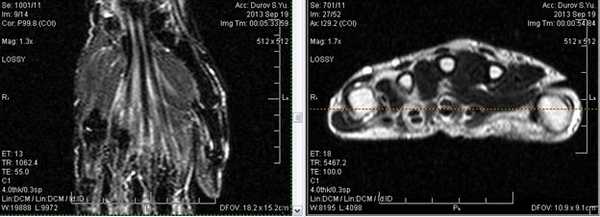

МРТ мышц и сухожилий локтевого сустава во фронтальной поверхности в норме

Локтевой сустав (МРТ анатомия)

Описание исследования 1 - головка лучевой кости 2 - венечный отросток локтевой кости 3 - локтевая кость 4 - локтевой отросток 5 - сухожилие трехглавой мышцы 6 - медиальная коллатеральная связка локтевого сустава 7 - лучевая коллатеральная связка локтевого сустава 8 - латеральная коллатеральная связка 9 - латеральный надмыщелок плечевой кости 10 - сухожилие двуглавой мышцы плеча 11 - плечевая мышца 12 - длинный лучевой разгибатель запястья 13 - блок плечевой кости 14 - локтевая мышца 15 - глубокий сгибатель пальцев 16 - локтевой сгибатель запястья 17 - трехглавая мышца 18 - кольцевидная связка лучевой кости 19 - двуглавая мышца плеча 20 - супинатор 21 - плечелучевая мышца 22 - круглый пронатор 23 - разгибатель пальцев 24 - лучевой сгибатель запястья 25 - поверхностный сгибатель пальцев 26 - локтевой нерв 27 - локтевой сгибатель запястья 28 - короткий лучевой разгибатель запястья 29 - общее сухожилие разгибателей 30 - общее сухожилие сгибателей и круглого пронатора 31 - бугристость лучевой кости 32 - головка плечевой кости 33 - медиальный надмыщелок плечевой кости 34 - гребень супинатора 35 - трапециевидная связка (lacertus fibrosus) 36 - наружная головка трехглавой мышцы плеча 37 - длинная головка трехглавой мышцы плеча 38 - медиальная головка трехглавой мышцы плеча 39 - общее сухожилие сгибателей